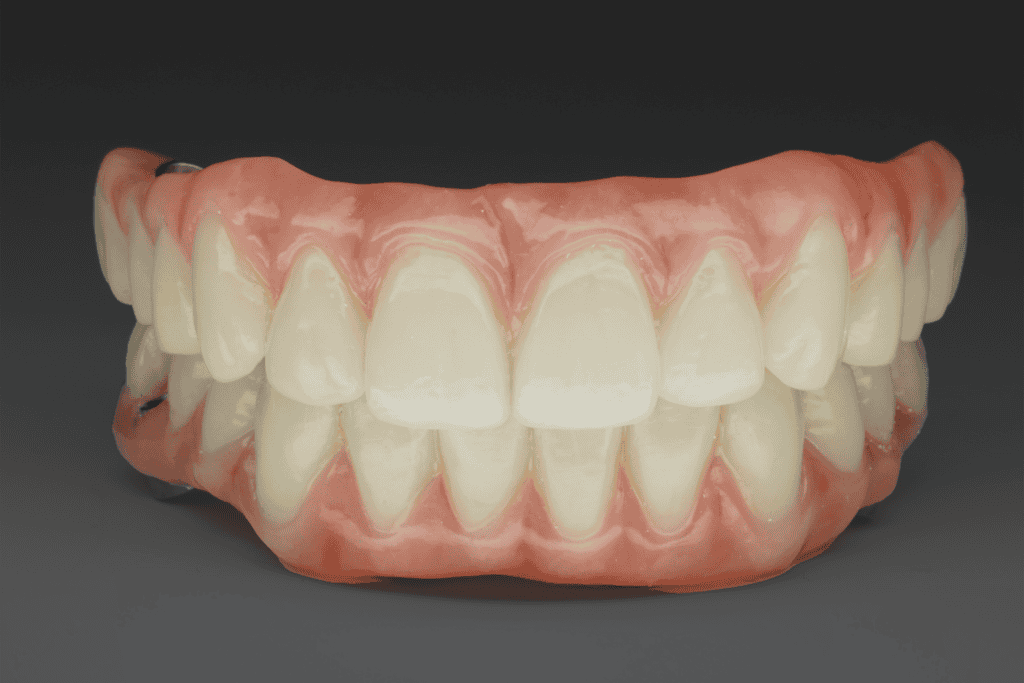

All-on-4 implants involve placing four strategically positioned implants in the jawbone to support a full arch of replacement teeth. This technique provides a stable, long-term solution, improving both dental function and overall oral health.

- Easier maintenance and greater comfort compared to traditional dentures

- Healthy, natural-looking teeth

- Prevention of further bone loss and maintenance of jawbone density

- Potential reduction in facial wrinkles caused by bone loss